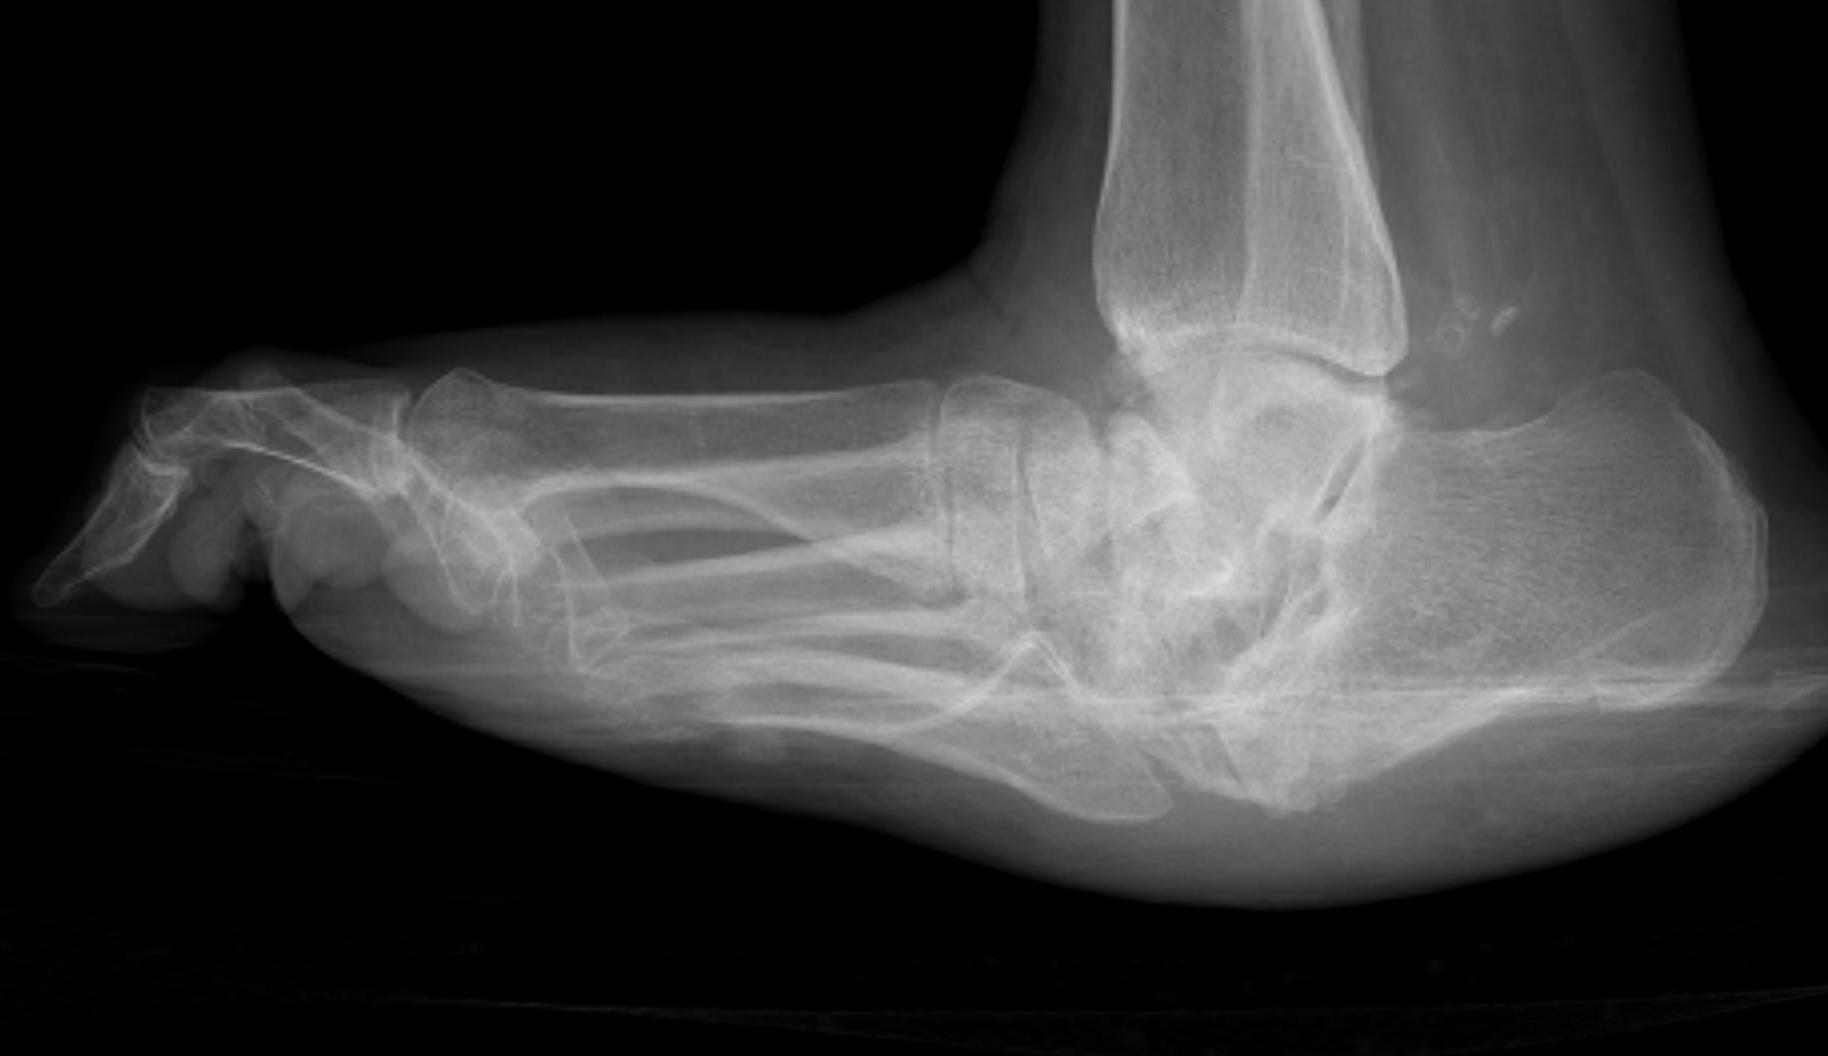

Xray

Midfoot collapse

Midfoot collapse and rocker bottom foot with small ulcer

Midfoot collapse with subluxation of midtarsal joints

Hindfoot collapse with ulcer